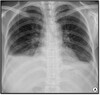

149

What pathology is seen here?

Metastatic Carcinoma; Canon ball lesions

150

Metastatic Carcinoma-miliary nodules

151